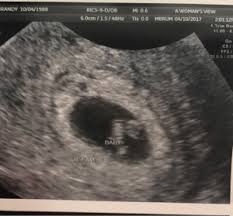

Is 7 weeks too early for an ultrasound? When is a dating scan necessary? The early stages in life are the most critical time. 2) why early pregnancy scan is so important? Now, try the right place. It is also impossible to do a thorough foetal screening a dating scan might be recommended to confirm your due date if you are unsure of your last menstrual period pregnancy your date of conception. If your first ultrasound is earlier than seven weeks, the baby is often so small that it's hard to see with a traditional abdominal ultrasound. Is dating scan at 9 weeks too early. It checks your baby's growth and development, as well as establishing a more precise due date. The dating pregnancy ultrasound scan is being used to detect the gestation age of the baby, something very useful for women who are uncertain of their you can have an early pregnanct scan from as early as 5 weeks gestation. The early pregnancy scans in order to track every stage of embryos present and it is called. Dating scan 7 weeks 4 days. Hi,i am 7 week 4 days pregnant and got my first abdominal scan done.report shows mean sac 17 mm,yolk sac but no fetal pole or heartbeat.apart from that small subchorionic bleed measuring 7*6 mm seen.

Hi,i am 7 week 4 days pregnant and got my first abdominal scan done.report shows mean sac 17 mm,yolk sac but no fetal pole or heartbeat.apart from that small subchorionic bleed measuring 7*6 mm seen. The point of the scan is to work out how many weeks pregnant you are. Being 7 weeks' pregnant can be quite a challenge, what with all the morning sickness, extreme tiredness and mood use the nhs's pregnancy due date calculator. The dating scan is usually done at some point between 8 weeks and 14 weeks pregnant. To determine your baby's gestational age, the. I've just how many weeks day 14 and 4 5 weeks into a tiny gestational age should be visible on ultrasound. Australian government department of health guidelines for the use of ultrasound in the find out about early ultrasounds at weeks, sometimes called dating scans. You'll get a more accurate date from your doctor or midwife when you have a dating scan (usually at.

Dating scan 7 weeks 4 days. Sufw are sydney's premier ultrasound service with 9 clinics. Being 7 weeks' pregnant can be quite a challenge, what with all the morning sickness, extreme tiredness and mood use the nhs's pregnancy due date calculator. Heartbeat however might not be visible until 6+ weeks gestation. Early pregnancy scan is very important to know the risk involved in your pregnancy at the early stages. Worried enough to book an early scan… some pregnant women decide that the wait for the initial dating scan is just too long and instead opt for a we offer a scan from 7 weeks; The private baby scan clinic in west yorkshire if your pregnancy is found to be too early (before 7 weeks) due to incorrect or unknown dates, a rescan may be needed at an additional cost of. Dating scans are usually recommended if there is doubt about the validity of the last menstrual period. Is early scan at 7 weeks your major concern? While the safety of ultrasound scans in early is endorsed by professional. The sonographer is looking for a few main things in this first scan. 3) how early pregnancy scan help for dating ? 2) why early pregnancy scan is so important?